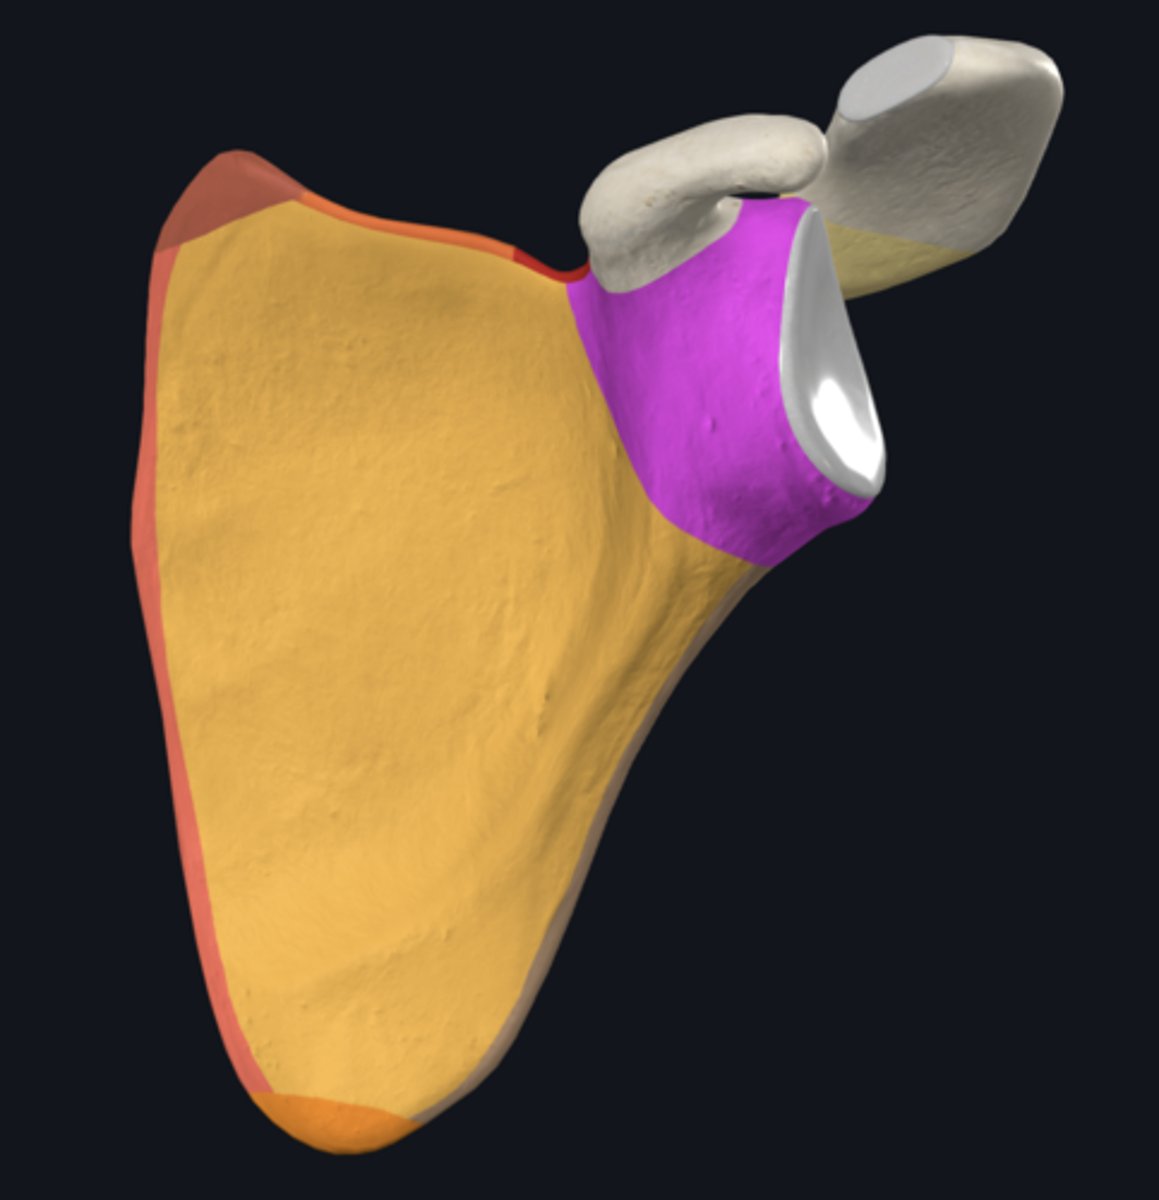

Acromion

Coracoid process

posterior surface of scapula

acromial angle

clavicular facet

glenoid fossa

infraglenoid tubercle

infraspinous fossa

spine of scapula

supraspinous fossa